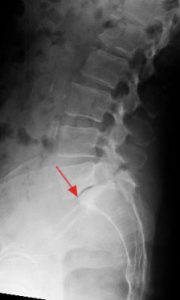

Spondylolisthesis is a spinal condition where one vertebra slips forward over the one below it due to a fracture, degeneration, or structural weakness in the spine. This forward slippage causes nerve compression, leading to lower back pain, leg pain, tingling, and difficulty standing or walking.